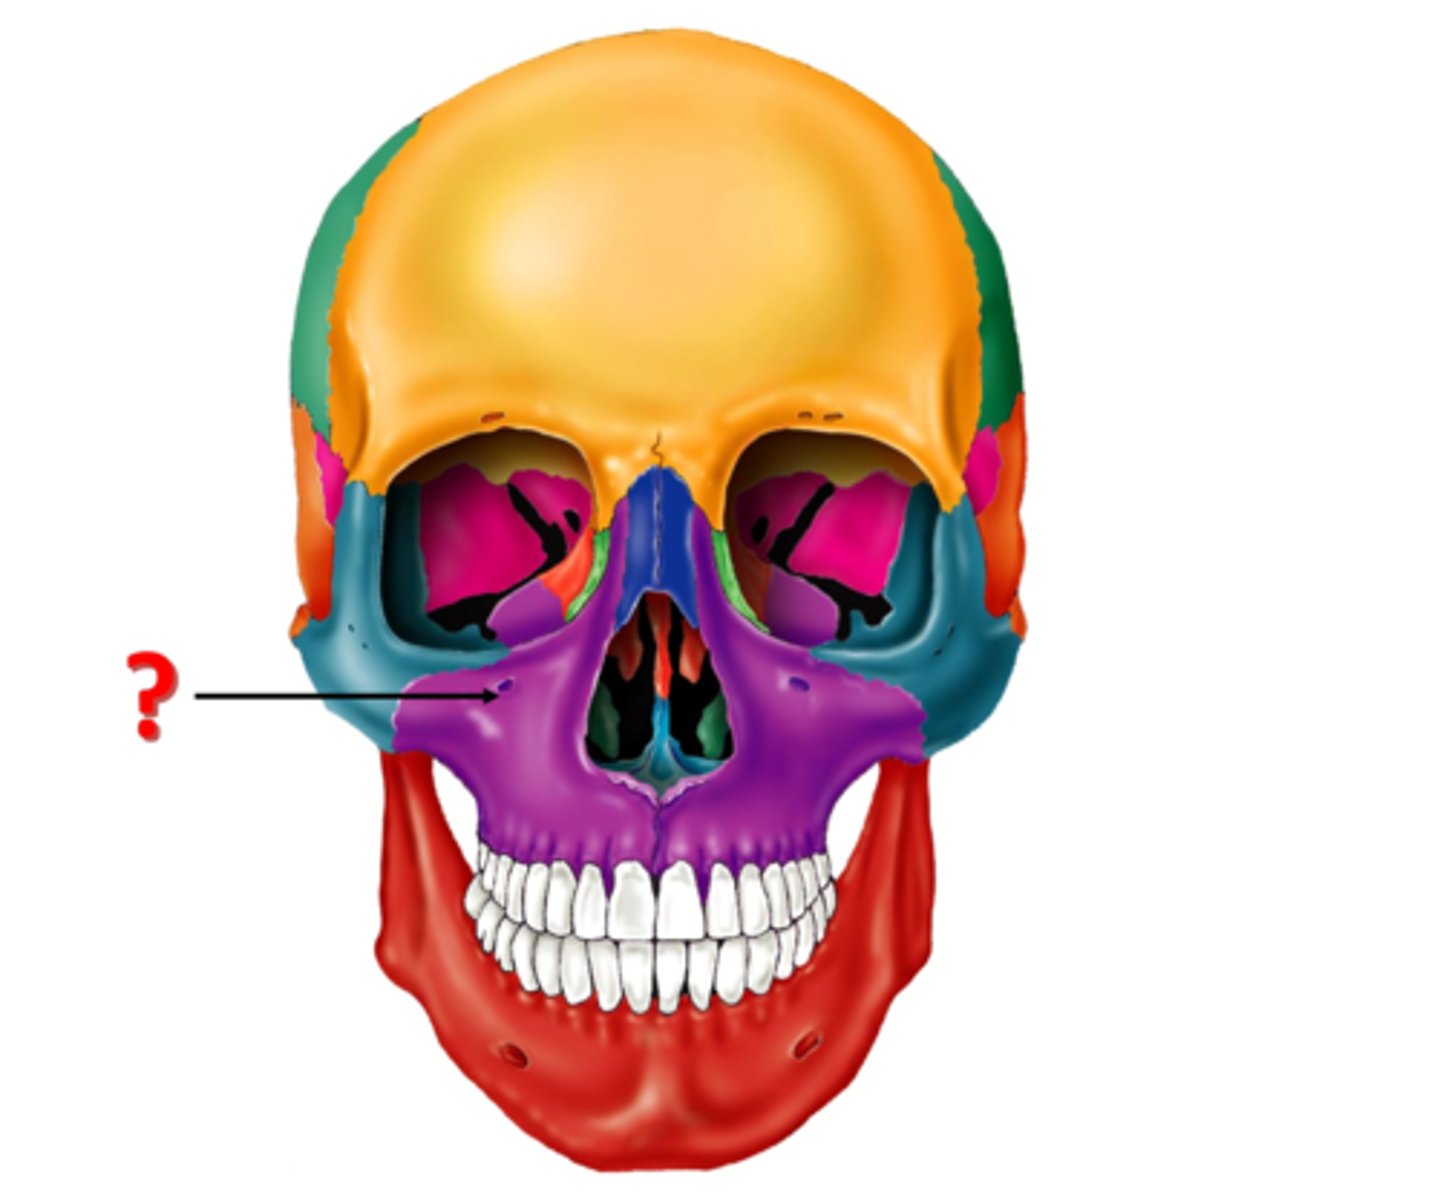

Parts of the Skull

39 Terms

1

New cards

Frontal Bone

2

New cards

Parietal Bone

3

New cards

Temporal Bone

4

New cards

Coronal Suture

5

New cards

Nasal Bone

6

New cards

Sphenoid Bone

7

New cards

Lambdoid Suture

8

New cards

Squamous Suture

9

New cards

Occipital Bone

10

New cards

Zygomatic Process

11

New cards

Mastoid Process

12

New cards

Styloid Process

13

New cards

Ethmoid Bone

14

New cards

Lacrimal Bone

15

New cards

Zygomatic Bone

16

New cards

Maxilla

17

New cards

Mandible

18

New cards

Mental Foramen

37

New cards

infraorbital foramen

38

New cards

supraorbital foramen